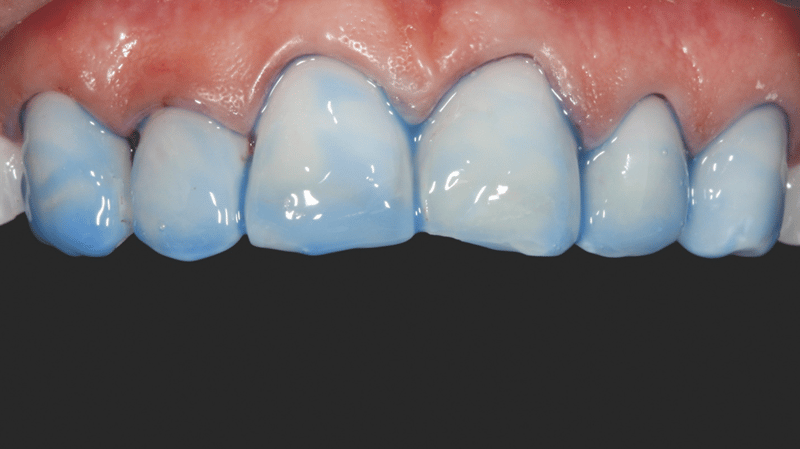

- Aanbrengen van de composiet: Transcend-composiet in de B1D-kleur werd aangebracht op 2/3 van de incisale rand, geleidelijk uitdunnend richting het gebied van de gingiva. In de buurt van het gingivale derde deel werd de Universal Body-kleur (UB) aangebracht. De restauratie werd verder afgewerkt met lagen Enamel White (EW) en een kleine hoeveelheid UB aan de gingivarand, voor een natuurlijke overgang.